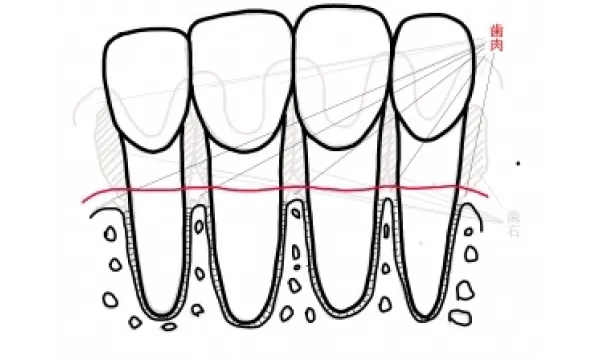

歯周病治療を行った結果、炎症がコントロールされた状態とは、炎症がなくなり(歯肉からの出血がなくなり)、最近との共生関係が確立(細菌がいなくなるのではなく影響がなくなる)その環境が永続しやすいような状態(浅いポケット)になることです。 残念ながらそれは、以前のように歯の間が歯肉に満たされ、骨が上まである状態ではありません。吸収してしまった骨は基本的には元には戻らず、歯肉は下がった状態で安定します。図に書くと以下のようになります。

治療によりコントロールできた状態

歯周病の状態に対し、患者さんのブラッシングが解消、歯科医院側では歯石取りとみがき残した部分のクリーニング、場合によっては手術を行って磨きやすい環境に変えてそれを持続すると、このように変わります。 つまり、歯肉は腫れがなくなり、溶け続けていた骨は安定して固まり、骨の2~3ミリ上に歯肉が炎症が無い状態です。残念ながら、骨も歯肉も増殖せず、元の位置に回復とはいきません。これが歯周病からの治癒像です。 事故で手や足がなくなった人が再生しないのと同じように、これが現在の限界なのです。